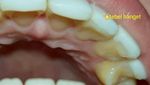

Celah yang terbentuk karena ukuran lapisan veneer yang tidak sesuai jadi tempat sisa makanan menumpuk di gusi. (Foto: Instagram/drgastridk/korbantukanggigi)